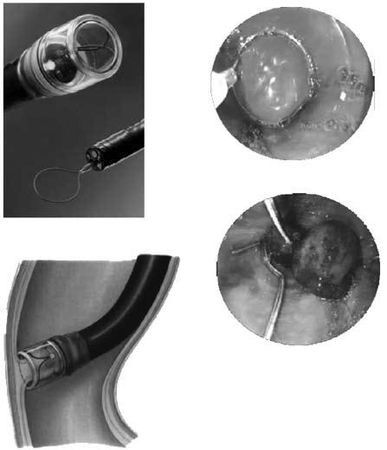

Рис. 85. Эндоскопическое лигирование варикозных вен пищевода

Для каждого вида кровотечения применяют свой метод гемостаза. Важно выбрать адекватный способ, поскольку второй попытки остановки кровотечения может и не представиться. Для определения источника кровотечения используют срочную фиброэзофаго-гастродуоденоскопию (ФЭГДС), во время которой подтверждают диагноз варикозного расширения вен пищевода, определяют зону нарушения целостности вены и интенсивность кровотечения. При умеренном кровотечении из варикозных вен пищевода, синдроме Мэллори-Вейса или язвы двенадцатиперстной кишки сразу может быть предпринята попытка его эндоскопической остановки. Наиболее эффективным методом остановки кровотечения из варикозных вен пищевода является их эндоскопическое лигирование. При этом эффективность метода достигает 90 %, а количество рецидивов составляет примерно 10 % (рис. 85).

Баллонная тампонада зоны кровотечения позволяет временно его остановить, после этого проводится гемостатическая терапия и восполняется кровопотеря. Через сутки давление в баллонах снижают. При остановке кровотечения могут быть предприняты попытки эндоскопической профилактики кровотечения путем паравазальной склеротерапии (при этом эффективность метода составляет около 90 %, а рецидивы кровотечения возникают почти в 30 % случаев) или эндоскопического лигирования вен пищевода (рис. 85; рис. 87).